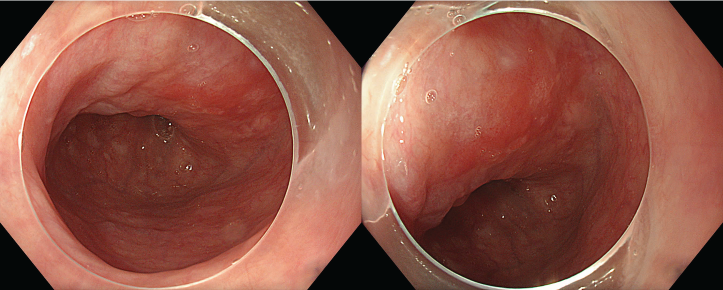

Quan sát với WLI thấy miệng nối thực quản – dạ dày quan sát ở vị trí cách cung răng trên khoảng 20 cm, niêm mạc nhẵn, quai nối lưu thông tốt. Trong khi đó, tại đoạn thực quản cách CRT 17–18cm xuất hiện một tổn thương dạng mảng đỏ, kích thước khoảng 15mm. Tổn thương có hình thái đại thể phù hợp với dạng 0-IIa (tổn thương nhô nhẹ trên niêm mạc – slightly elevated).